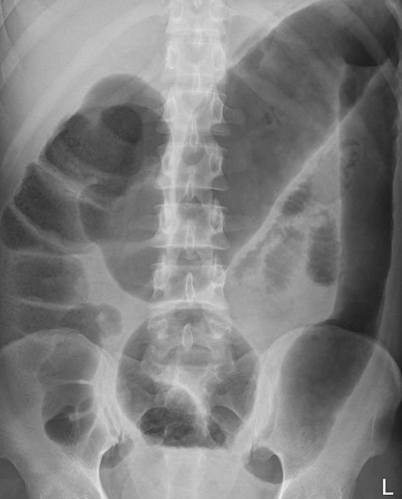

Toxic megacolon is defined as the dilatation of the transverse colon to a diameter of more than _____ cm